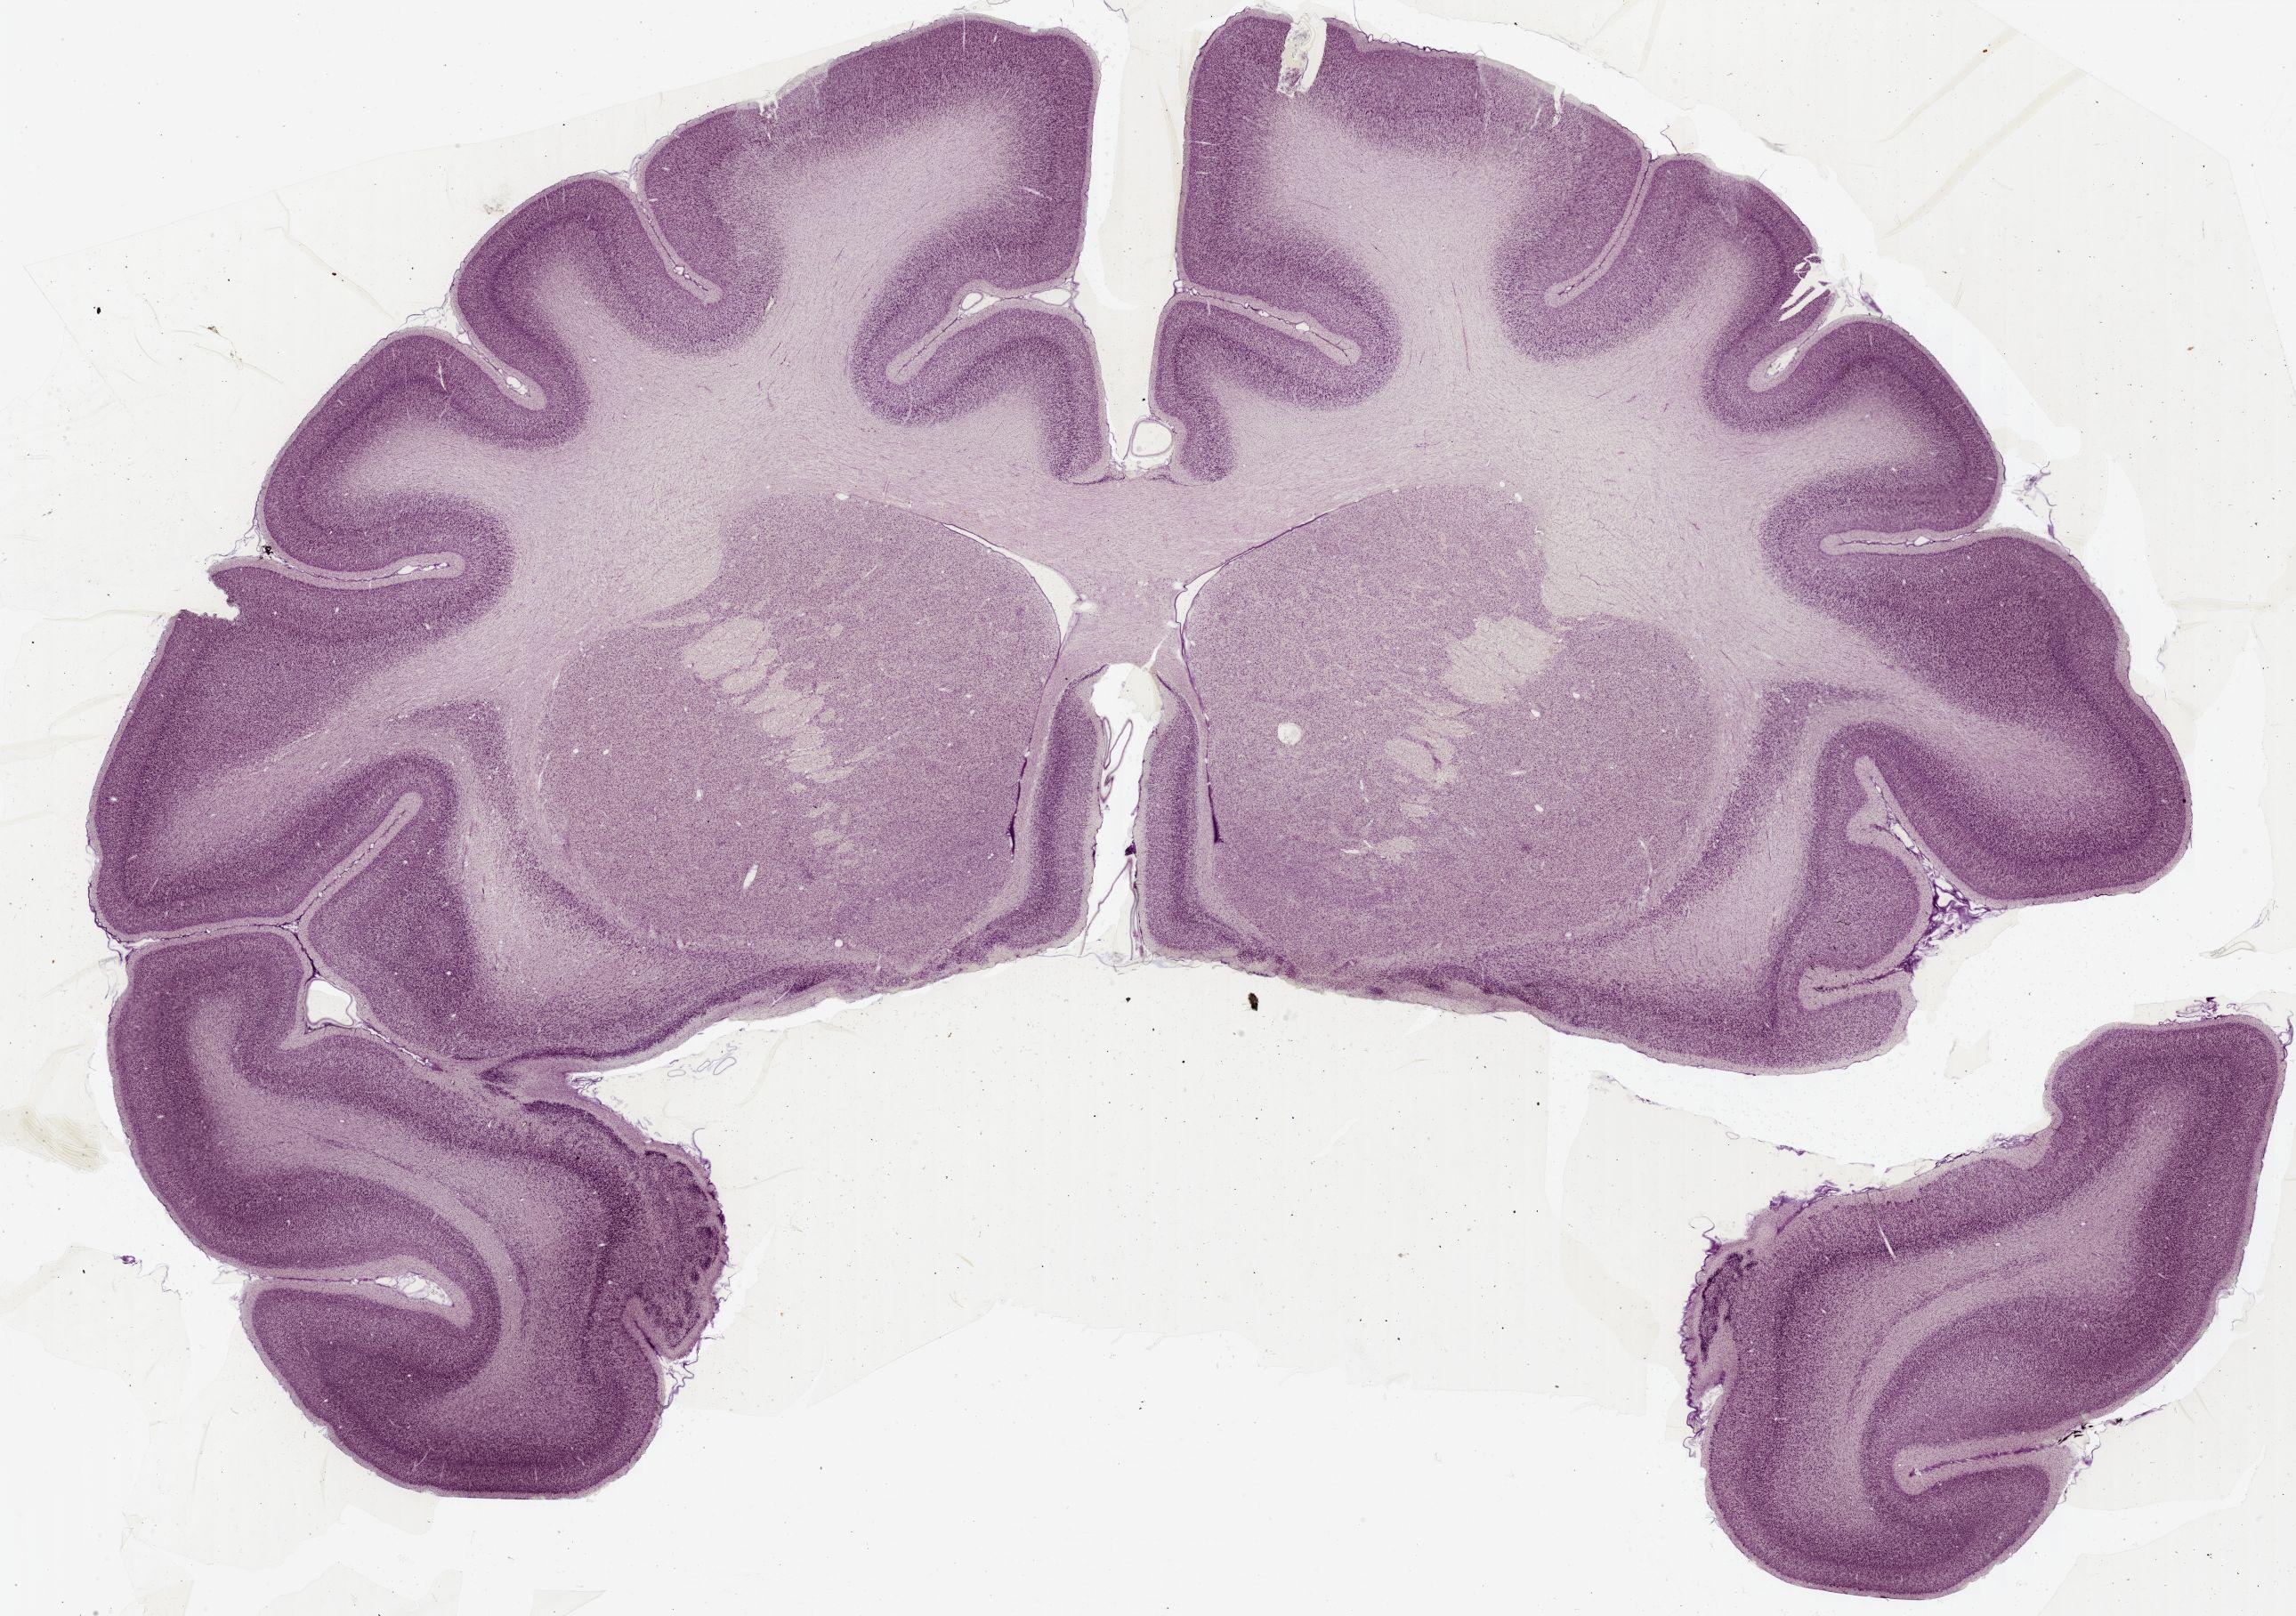

Datasets -> Macaca Mulatta -> Nissl, coronal, histo, Whole-Brain, adult [ Metadata ] · Source: Edward G. JonesDisplaying Sections 1 thru 40 of 56 Sections for this DatasetPages: 1 2 1339 - labeled 1301 - labeled 1251 - labeled 1201 - labeled 1151 - labeled 1102 - labeled 1051 - labeled 1040 - labeled 1020 - labeled 1006 - labeled 1001 - labeled 0982 - labeled 0975 - labeled 0958 - labeled 0951 - labeled 0941 - labeled 0924 - labeled 0920 - labeled 0901 - labeled 0894 - labeled 0878 - labeled 0875 - labeled 0859 - labeled 0851 - labeled 0845 - labeled 0824 - labeled 0823 - labeled 0801 - labeled 0800 - labeled 0785 - labeled 0781 - labeled 0771 - labeled 0770 - labeled 0732 - labeled 0721 - labeled 0720 - labeled 0701 - labeled 0682 - labeled 0680 - labeled 0666 - labeledPages: 1 2